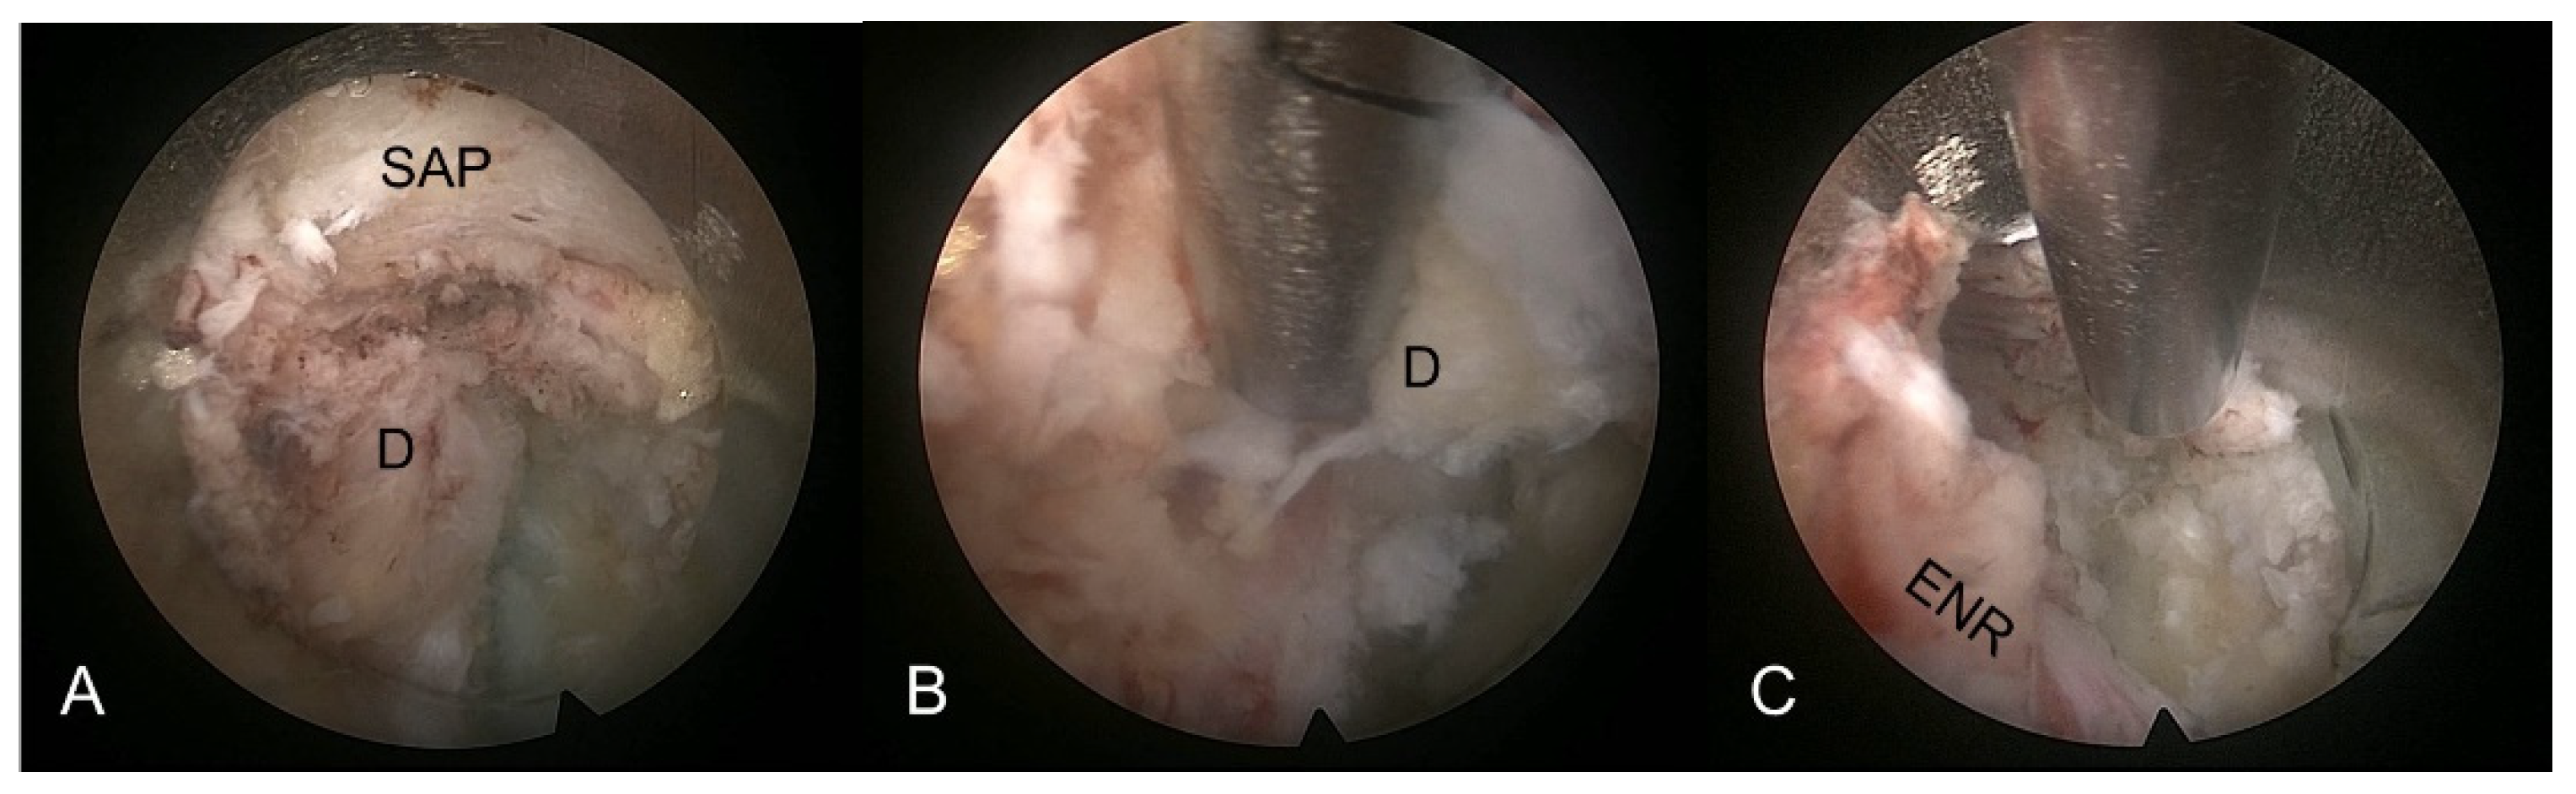

2.2.3. Selective Discectomy under Endoscopic Visualization